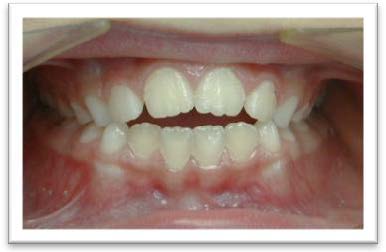

Béance antérieure